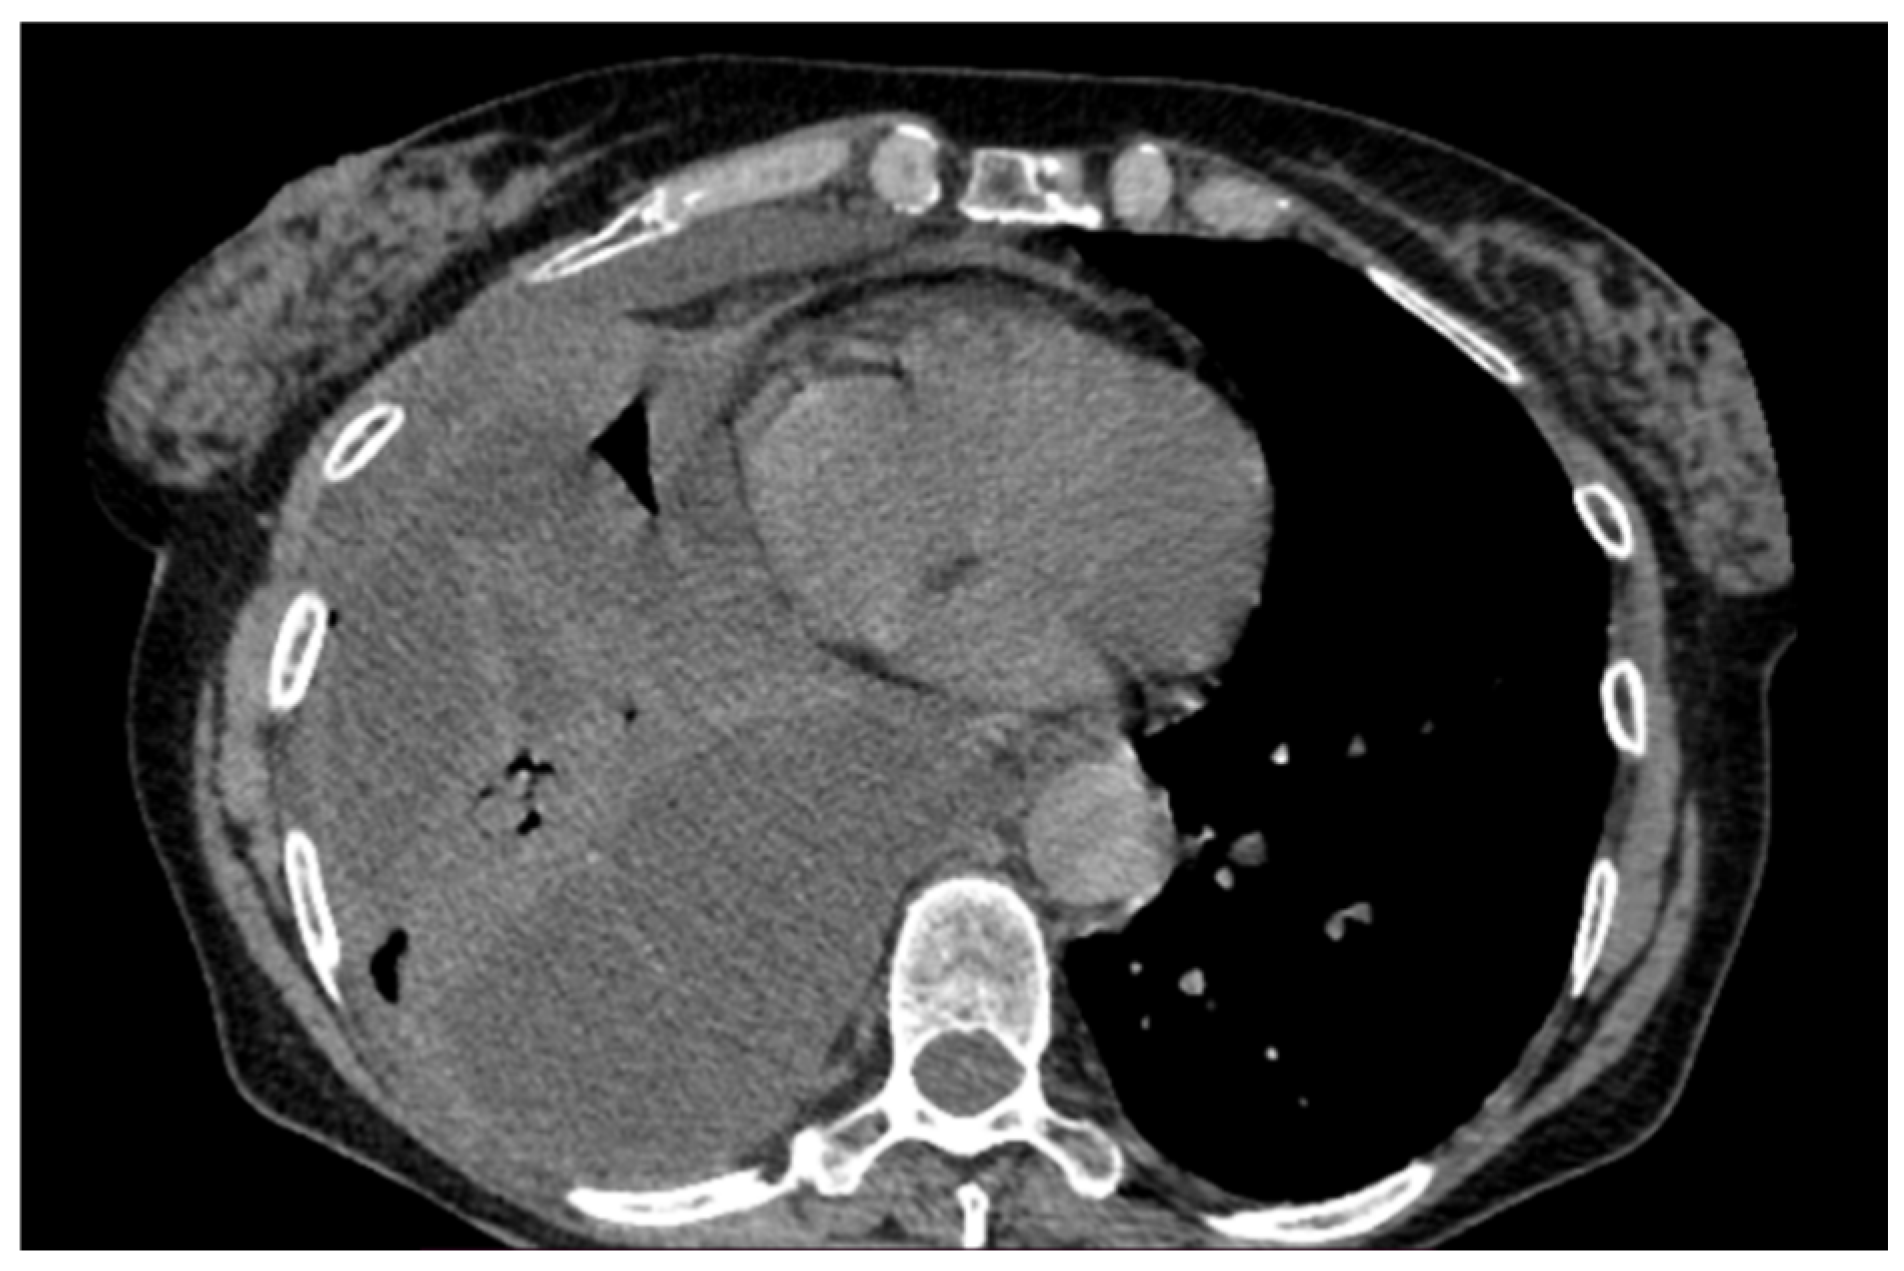

A 61-year-old female patient with obesity, discoid lupus, bipolar disorder, arterial hypertension, and hypothyroidism was admitted to our Respiratory Unit for respiratory failure and evidence of a large complex PEff on her chest CT, which also revealed complete atelectasis of the right lower lobe (RLL) and almost-complete atelectasis of the middle lobe (ML) and right upper lobe (RUL) (Figure 6). There was also a solid tissue surrounding the right main bronchus and its main branches, which was suspected to be neoplastic. It had a central hypodense area consistent with necrosis.

Peripheral enhancement of the pleural layers was also observed.

Figure 6. Chest CT scan of the mediastinal window in the coronal (A) and axial (B) plane, showing a large right pleural effusion, occupying almost the entire hemithorax with organized appearance. There is also a complete right lower lobe atelectasis and almost-complete right middle and upper lobe atelectasis with sparing of anterior sectors.